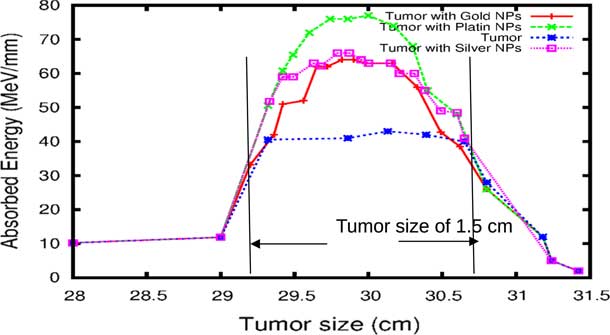

The comparison of our results concerning the energy deposited into a tumour in the presence of NMs is represented in Figure 9. As the figure shows, the gold and silver enhance the proton therapy and increase the absorbed energy in the tumour up to 55%, on the other hand, platinum increases the absorbed energy up to 80%. Lin et al.Reference Lin, McMahon, Scarpelli, Paganet and Schuemann 25 have compared radiotherapy with protons and radiotherapy with photons and concluded that the proton therapy can enhanced significantly the absorbed dose only if the GNPs are in close proximity to the biological target.

Figure 9 The deposited energy of a polyenergetic proton beam into the tumour with adding nanomaterials (NMs). Notes: The proton beam energy is ranging between 116 and 126 MeV in the tumour without any NMs, and between 116 and 130 MeV in the tumour with gold NPs (GNPs) and silver NPs (AgNPs). In the case of platinum NPs (PtNPs), the proton beam energy is ranging between 116 and 132 MeV.